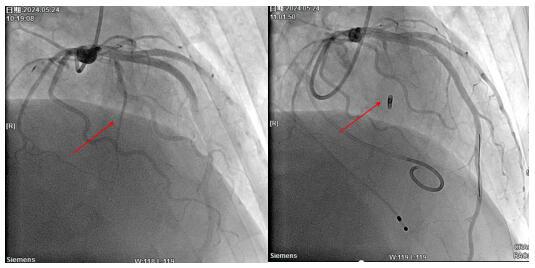

手術(shù)由心血管內(nèi)科副主任董學(xué)濱及范海副主任醫(yī)師實施完成,術(shù)中穿刺股靜脈植入臨時起搏器保護,穿刺右側(cè)橈動脈行冠脈造影再次確定需要封堵的第一間隔支,在Runthrough導(dǎo)絲指引下送入OTW球囊,6atm封堵第一間隔支中段,后通過OTW球囊緩慢注入聚乙烯栓塞微球2ml及2mm×8cm彈簧圈1枚,復(fù)查造影提示封堵效果滿意,第一間隔支自中段開始完全閉塞,前降支血流通暢。術(shù)后患者生命體征穩(wěn)定,術(shù)后第二天拔除臨時起搏器,術(shù)后第四天患者可自行下床活動,胸痛癥狀完全緩解。術(shù)后復(fù)查心臟彩超提示室間隔厚度及左室流出道壓差較前明顯下降,手術(shù)成功。

術(shù)前造影定位間隔支 術(shù)中封堵間隔支影像